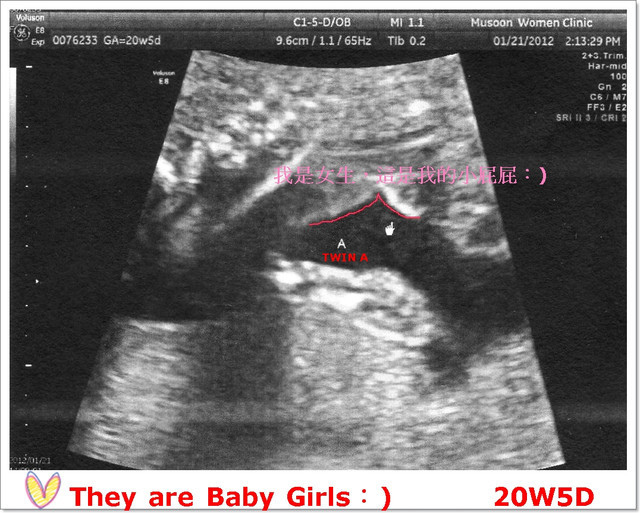

【20W5D】TWIN A,431克、心跳144/1分鐘;TWIN B,341克、心跳138/1分鐘,

然後,醫生就緊盯著A寶寶的二腿之間瞧,哈哈哈哈~好害羞啊!

「嗯...好像沒有小雞雞哦!所以非常有可能是女生哦!」

看了兩次,非常的確定A寶寶是女娃♥